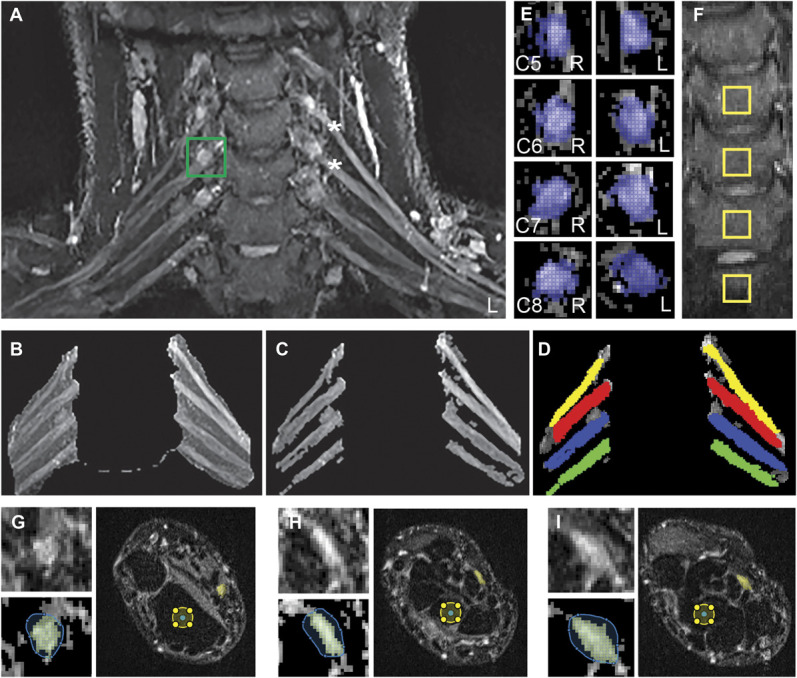

Abstract: Whiplash injury is associated with high socioeconomic costs and poor prognosis. Most people are classified as having whiplash-associated disorder grade II (WADII), with neck complaints and musculoskeletal signs, in the absence of frank neurological signs. However, evidence suggests that there is a subgroup with underlying nerve involvement in WADII, such as peripheral neuroinflammation. This study aimed to investigate the presence of neuroinflammation in acute WADII using T2-weighted magnetic resonance imaging of the brachial plexus, dorsal root ganglia and median nerve, and clinical surrogates of neuroinflammation: heightened nerve mechanosensitivity (HNM), raised serum inflammatory mediators, and somatosensory hyperalgesia. One hundred twenty-two WADII participants within 4 weeks of whiplash and 43 healthy controls (HCs) were recruited. Magnetic resonance imaging T2 signal ratio was increased in the C5 root of the brachial plexus and the C5-C8 dorsal root ganglia in WADII participants compared with HCs but not in the distal median nerve trunk. Fifty-five percent of WADII participants had signs of HNM. Inflammatory mediators were also raised compared with HCs, and 47% of WADII participants had somatosensory changes on quantitative sensory testing. In those WADII individuals with HNM, there was hyperalgesia to cold and pressure and an increased proportion of neuropathic pain. Many people with WADII had multiple indicators of neuroinflammation. Overall, our results present a complex phenotypic profile for acute WADII and provide evidence suggestive of peripheral neuroinflammation in a subgroup of individuals. The results suggest that there is a need to reconsider the management of people with WADII.